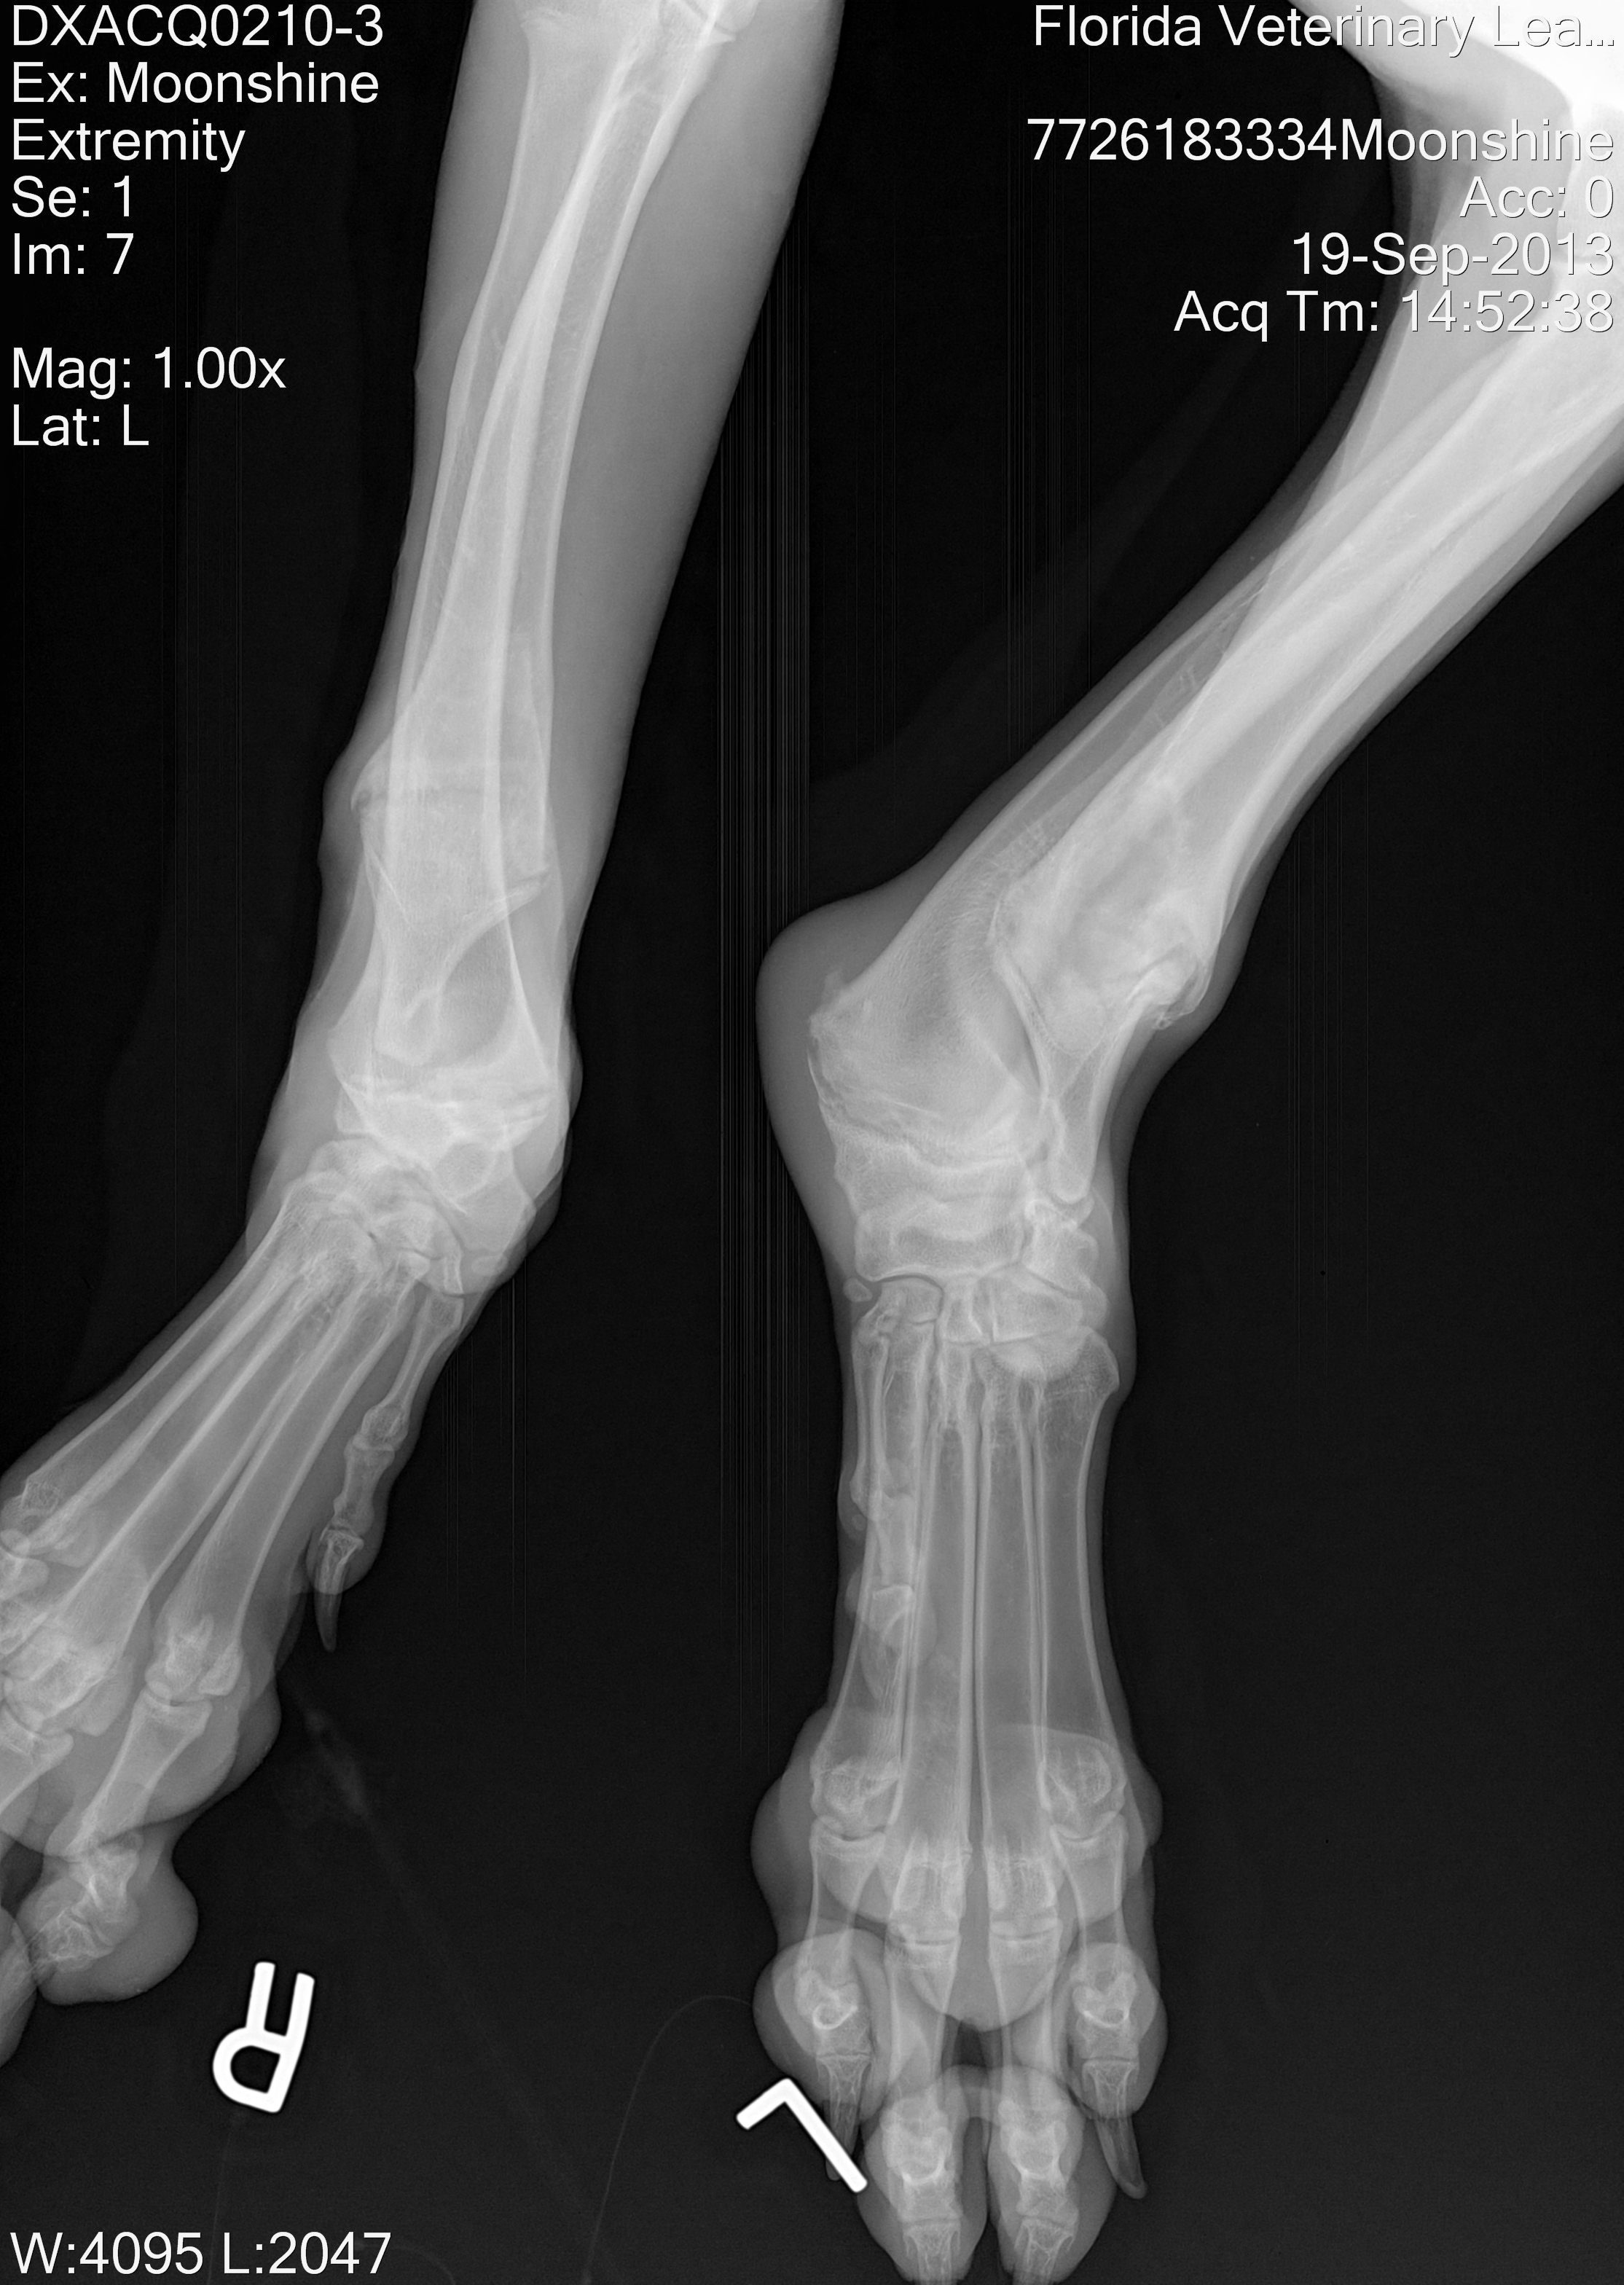

MOONSHINE:

September 19th, 2013

Moonshine is one of the most heartbreaking cases we have recently seen; this poor 10 month old Harlequin Great Dane girl was abandoned at an animal control facility due to a birth defect on her front legs, she was there for several months unable to be adopted and was already removed from the adoption floor (the first two pictures below were taken when we first saw her in her kennel), we simply couldn't leave her behind. Moonshine is currently scheduled to have corrective surgery in November 2013 for her first leg and mid December for her second leg.

(More updates and after surgery pictures will be updated soon)